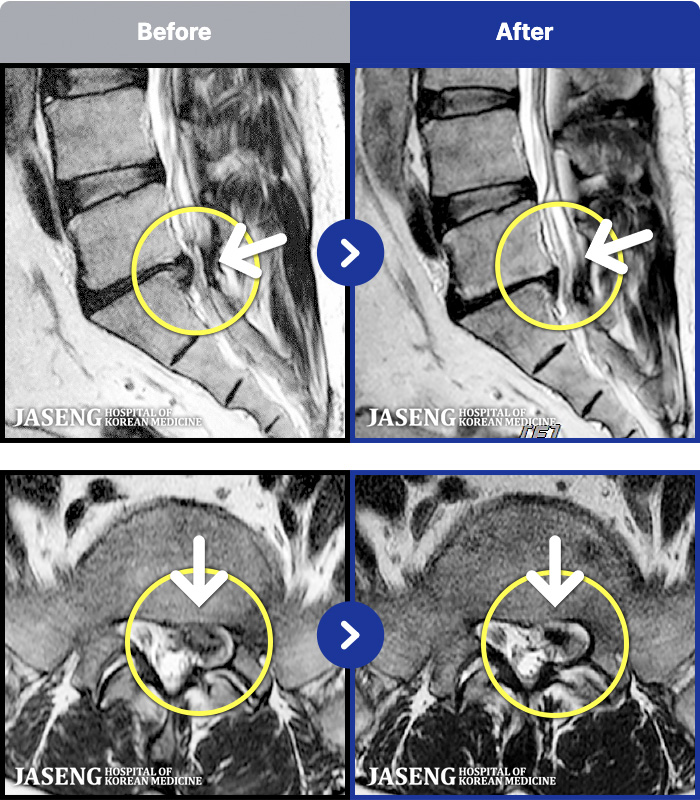

1,287 MRI ũ ʸ Ȯϼ.